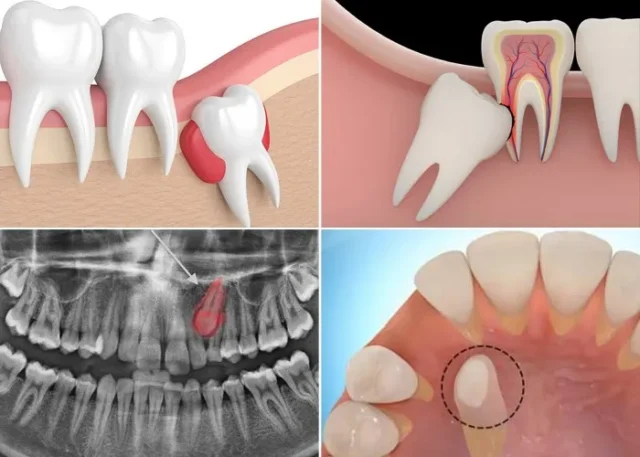

Chụp X-quang để xác định vị trí và hướng mọc của răng

Chụp phim toàn cảnh (Panorex): Giúp bác sĩ có cái nhìn tổng quát về sự sắp xếp của tất cả các răng, xác định vị trí chung của răng ngầm.

Chụp phim Cone Beam CT (CBCT): Tại Nha khoa Dr. Green, chúng tôi ưu tiên sử dụng CBCT vì nó cung cấp hình ảnh 3 chiều chi tiết. Phim CBCT giúp bác sĩ xác định chính xác:

- Vị trí và độ sâu: Răng nằm ở mặt môi hay mặt khẩu cái (vòm miệng), nằm cách mặt nhai bao nhiêu.

- Hướng mọc: Răng nằm ngang, xiên hay thẳng đứng.

- Mối quan hệ với các cấu trúc lân cận: Đặc biệt là mối quan hệ với chân răng cửa bên (để đánh giá nguy cơ tiêu chân).